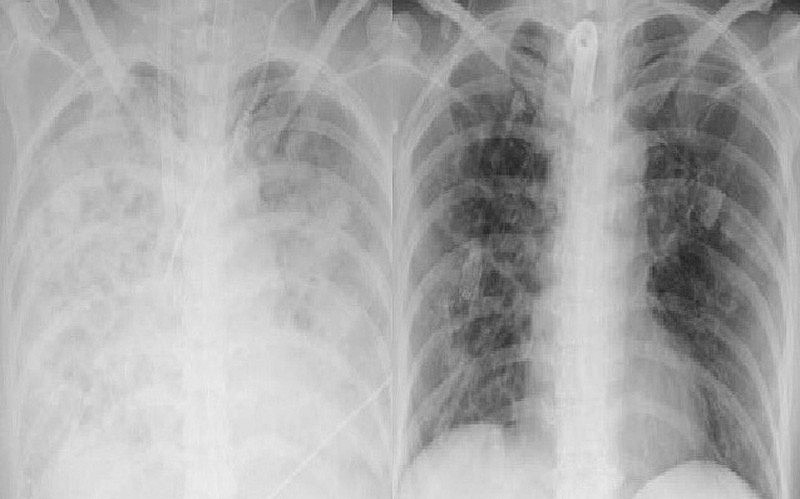

Theo ThS.BS Nguyễn Bá Cường - Trung tâm Hồi sức tích cực, Bệnh viện Bạch Mai, khi vào Trung tâm, tình trạng bệnh nhân rất nặng nề, sốt cao liên tục, sốc nhiễm khuẩn nặng, oxy máu giảm rất thấp, X-quang phổi mờ trắng xóa cả 2 bên phế trường, test nhanh cúm B dương tính. Điều đặc biệt là mặc dù nhiễm cúm nhưng tình trạng nhiễm vi khuẩn trên xét nghiệm rất cao, kèm theo đó là số lượng bạch cầu giảm trầm trọng còn 0.750 G/L (Bình thường 4.0-10.0 G/L).

| Hình ảnh phim phổi bệnh nhân trước và sau điều trị. Ảnh: BVCC |